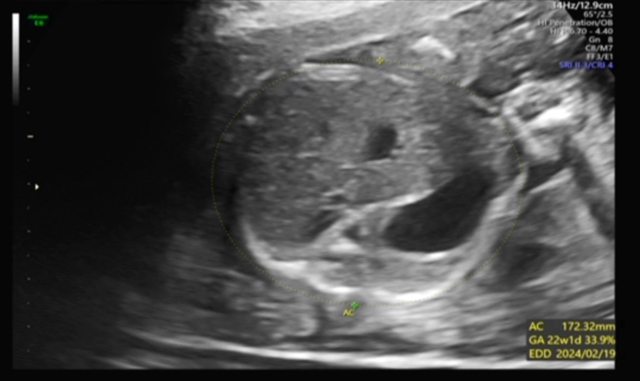

昨天去產檢,醫生覺得寶寶的胃偏大之後要注意觀察 我搜尋了一下好像只有看到胃太小的文,請問大家有沒有遇過類似情況? 我後來看了一下22週的高層次照片,那時候寶寶也是胃大大的,但那時只說是寶寶可能剛 吃飽 https://i.imgur.com/amlKp09.jpg

每一胎的狀況真的不一樣,這次第二胎先歷經羊水少週數小三週,到現在追到剩小一週, 但昨天醫生又提醒胃好像偏大,只希望二寶可以健康平安出生~ -- ※ 發信站: 批踢踢實業坊(ptt-club.com.tw), 來自: 101.12.24.40 (臺灣) ※ 文章網址: https://ptt-club.com.tw/BabyMother/M.1700797726.A.8D2